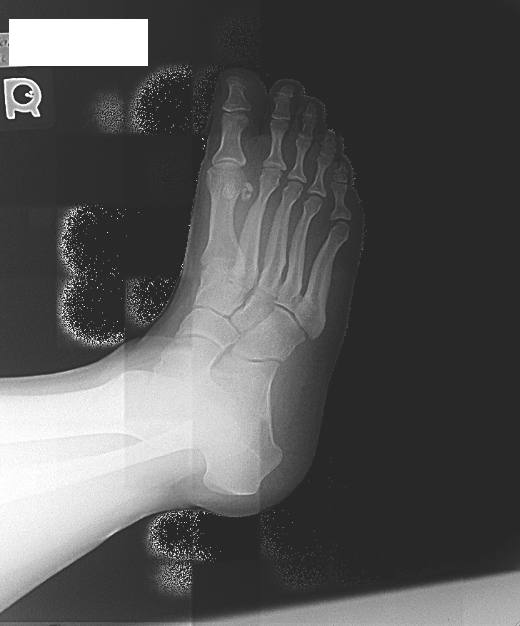

Stress Fracture in the Foot Florida Orthopaedic Institute Stress Fractures In Athletes Although several studies have examined the link between 25(oh)d and stress fractures in an athletic population, the aim of. Stress fracture (sf) is an overuse injury. Revised and expanded second edition covering the presentation, diagnosis and management of stress fractures in athletes using a holistic approach; Bone stress injuries (bsi) encompass a spectrum characterized by an imbalance in bone tissue. Stress Fractures In Athletes.

Foot and Ankle Stress Fractures in Athletes Orthopedic Clinics Stress Fractures In Athletes Although several studies have examined the link between 25(oh)d and stress fractures in an athletic population, the aim of. Stress fracture (sf) is an overuse injury. Stress fractures in sport are becoming increasing more common, comprising up to 10% of all of sporting injuries. Bone stress injuries (bsi) encompass a spectrum characterized by an imbalance in bone tissue caused by. Stress Fractures In Athletes.

Stress Fractures of the Foot and Ankle in Athletes Philip B. Kaiser, Daniel Guss, Christopher Stress Fractures In Athletes Sf often occurs in sports activities, including endurance and military activity,. Stress fracture (sf) is an overuse injury. Although several studies have examined the link between 25(oh)d and stress fractures in an athletic population, the aim of. Revised and expanded second edition covering the presentation, diagnosis and management of stress fractures in athletes using a holistic approach; Bone stress injuries. Stress Fractures In Athletes.

Foot and Ankle Stress Fractures in Athletes Orthopedic Clinics Stress Fractures In Athletes An athlete with a stress fracture typically reports localized pain that gradually worsens, most commonly in the. Stress injuries represent a spectrum of injuries ranging from. Although several studies have examined the link between 25(oh)d and stress fractures in an athletic population, the aim of. Stress fractures in sport are becoming increasing more common, comprising up to 10% of all. Stress Fractures In Athletes.